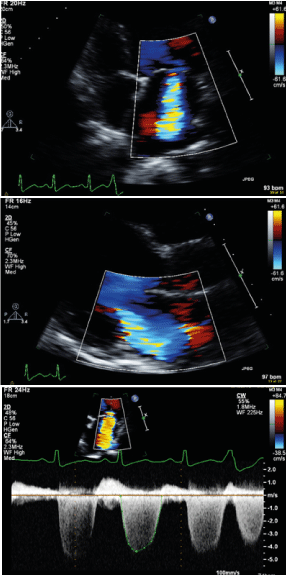

On examination, his vital signs were unremarkable, and rest of his examination is significant for classic findings of heart failure: jugular venous distension, lung crackles bilaterally, apical pansystolic murmur and bilateral lower extremity edema. ECG showed sinus rhythm with multiple premature ventricular complexes (PVCs) and lateral T wave inversions (Figure 1). Echocardiography was performed and showed a severely reduced left ventricular ejection fraction (LVEF) of ~30.8% estimated by Simpson’s biplane with global hypokinesis and moderate to severe mitral regurgitation and moderate left atrial dilation (Figure 2). Additional work-up included a 24-hour holter, which showed frequent PVC burden (36.1%) with no evidence of sustained ventricular tachycardia.

Figure 2. Echocardiography with Color-Doppler showing moderate-severe mitral regurgitation